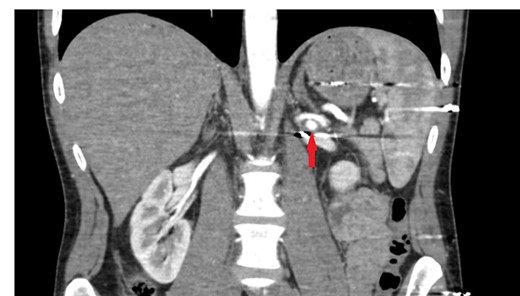

A 26-year-old male patient was brought to the emergency department due to a gunshot wound. He was hemodynamically stable; however, hematuric urine output was observed. In complete blood count, hemoglobin (Hb) and hematocrit (Hct) values were detected as 12.6 g/dl and 39.4%. The abdominopelvic computed tomography (CT) showed minimal laceration in liver segment 6, left retroperitoneal hematoma and two bullet cores adjacent to the left renal artery and lower pole of the left kidney. A CT angiography (CTA) was performed. This investigation revealed a bullet core and a 4-mm RAP in the middle of the left renal artery (Fig. 1).

The initial computerized tomographic angiography image of the bullet core adjacent to the middle segment of the left renal artery and the renal pseudoaneurysm.